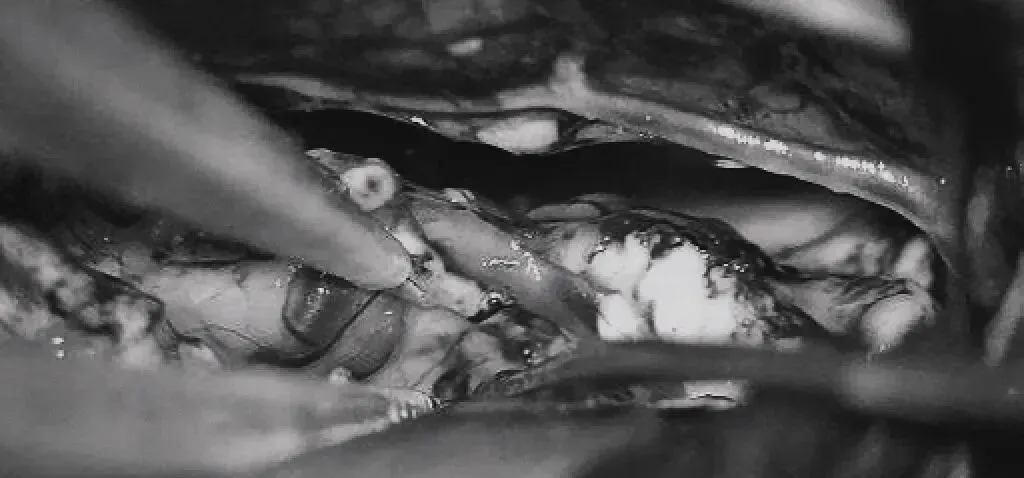

手术采用双额开颅+纵裂入路,在显微镜下细致分离大脑纵裂,暴露胼胝体及供血动脉。

随后切开胼胝体2.5cm,深入透明隔——这里是记忆、认知功能的关键区域,稍有不慎便可能导致永久性损伤。

将AVM后缘向前牵离穹窿。